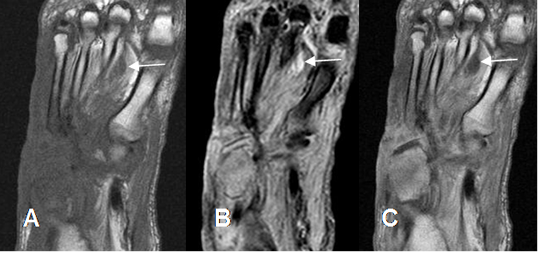

Fig 127 B. Osteomielitis.

A: RM coronal en T1, B: RM coronal en STIR y C: RM coronal en T1 con contraste. Igual paciente anterior. Cambios inflamatorios en los músculos y el tejido celular subcutáneo, sobre el medio pie. Los huesos cuboides, la cuña lateral y mitad inferior del 3º y 4º metatarsianos son hipointensos en T1, hiperintensos en STIR y realzan

con el contraste, por osteomielitis. Hay pequeña colección entre el 1º y 2º metatarsianos.